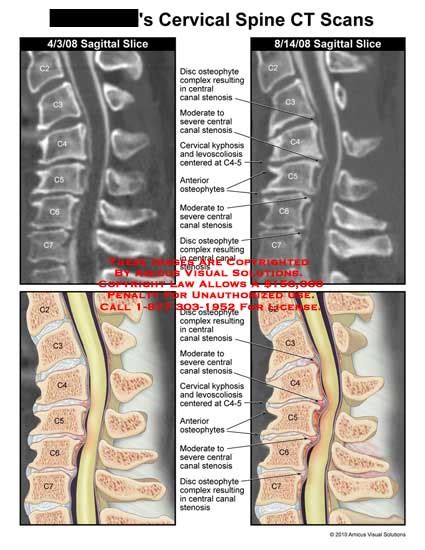

AMICUS Illustration of amicus,injury,mri,disc,osteophyte,complexes,c2 ...

AMICUS Illustration of amicus,injury,cervical,spine,CT,scans,disc ...